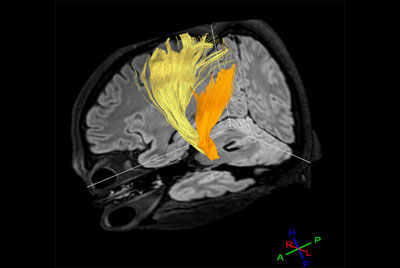

Comprehensive Brain with MultiBand SENSE DTI

Advanced Brain imaging

Advanced Neuro imaging - pCASL

Advanced Neuro MR - SWIp